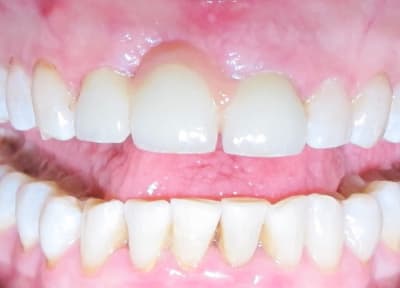

1er bridge full Zircone

Je suis prêt pour les critiques n'hésitez pas.

J'aurai bien aimé une photo sans l'amovible, mais à mon avis il était possible de faire autre chose qu'une fausse gencive céramique moche.

Si le patient est démuni, joli boulot.